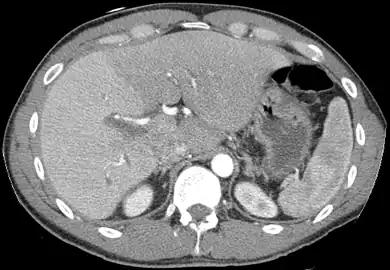

A CT scan in which the liver and portal vein are shown

With the recent advances of noninvasive imaging, living liver donors usually have to undergo imaging examinations for liver anatomy to decide if the anatomy is feasible for donation. The evaluation is usually performed by multidetector row computed tomography (MDCT) and magnetic resonance imaging (MRI). MDCT is good in vascular anatomy and volumetry. MRI is used for biliary tree anatomy. Donors with very unusual vascular anatomy, which makes them unsuitable for donation, could be screened out to avoid unnecessary operations.

MDCT image. Arterial anatomy contraindicated for liver donation

MDCT image. Portal venous anatomy contraindicated for liver donation

MDCT image. 3D image created by MDCT can clearly visualize the liver, measure the liver volume, and plan the dissection plane to facilitate the liver transplantation procedure.

Phase contrast CT image. Contrast is perfusing the right liver but not the left due to a left portal vein thrombus.